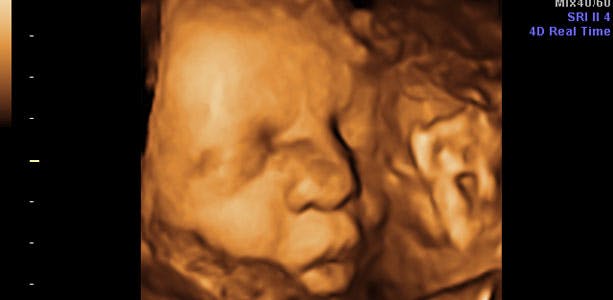

Gravid uge 34: Øget vægt

foto: jordemoder.dk

Måler omkring 43 cm, vejer cirka 2200 gram og kan boltre sig i en liter fostervand. Den primære ting, baby skal koncentrere sig, om er vægtøgning. Huden er ikke længere gennemsigtig, men dejlig lyserød. Skulle fødslen gå i gang, gør man ikke noget aktivt for at stoppe den efter uge 34+0, da baby nu i langt de fleste tilfælde er i stand til at trække vejret selv.